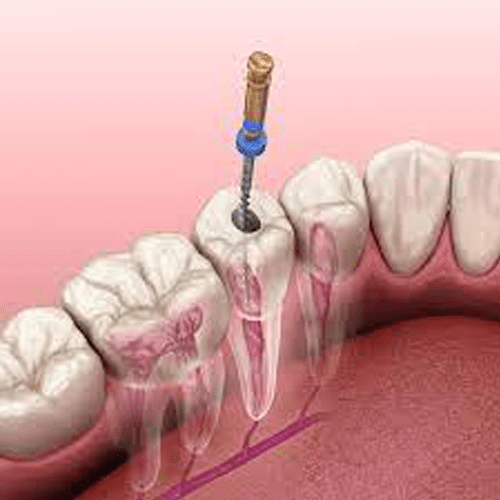

Our Root Canal Treatment is designed to eliminate infection from the tooth’s pulp, relieve pain, and restore dental health. For patients needing further intervention, we offer Re-Root Canal Treatment, which addresses complications from previous procedures. Additionally, our Post and Core services help rebuild and support teeth that are severely damaged, ensuring longterm stability.